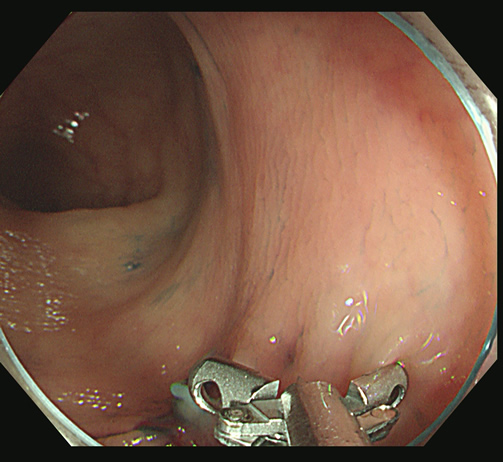

「Extended Cold法」で切除し、切除創を詳細に観察することが肝要です

「遺残の可能性」がわずかでもある場合は、「辺縁のトリミング」を追加します

「広めに取り過ぎた」位が安全であり、望ましいと考えています。